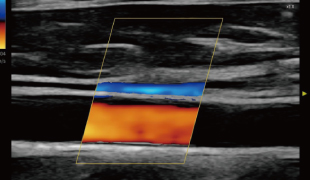

4つの表示モードを搭載

Bモードに加え、カラードプラモードを搭載し、血流の評価が可能。さらに、アプリケーションのアップデートにより、PWモード、Mモードを追加搭載。血流速度の計測や、コロナ禍において活用できる肺エコーにも対応しました。